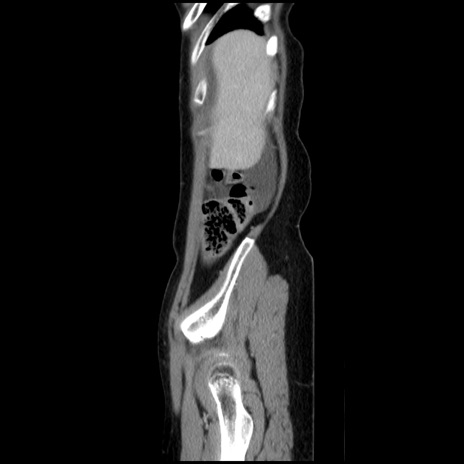

症例32(矢状断像)

【症例】40歳代 女性

【主訴】上腹部痛、嘔気・嘔吐

【現病歴】約9時間前頃から急に上腹部痛、嘔気、嘔吐が出現。改善しないため救急要請。

【既往歴】子宮頚癌(広汎子宮全摘術、放射線療法)、腸閉塞

【身体所見】腹部:平坦、軟、腸雑音亢進、上腹部を中心に腹部全体に圧痛あり。

【データ】WBC 8400、CRP 0.03